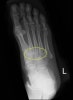

X-ray상 Lisfranc 관절에 spur, joint space narrowing, bone sclerosis가 나타납니다.

X-ray : Lisfranc 관절염(Lisfranc arthritis, Midfoot arthritis)